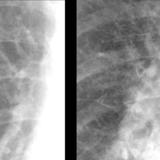

APE 4

Date: 11/05/2005

Views: 2939